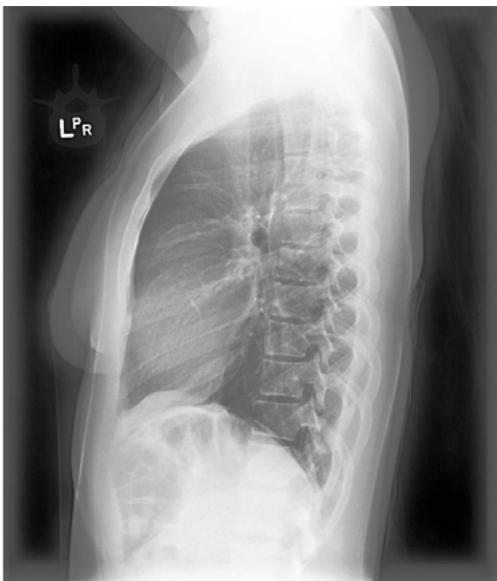

A: Frontal View

B: Lateral View Figure 2: Views of CXR in CheXpert Dataset (Source: Irvin et al, 2019).